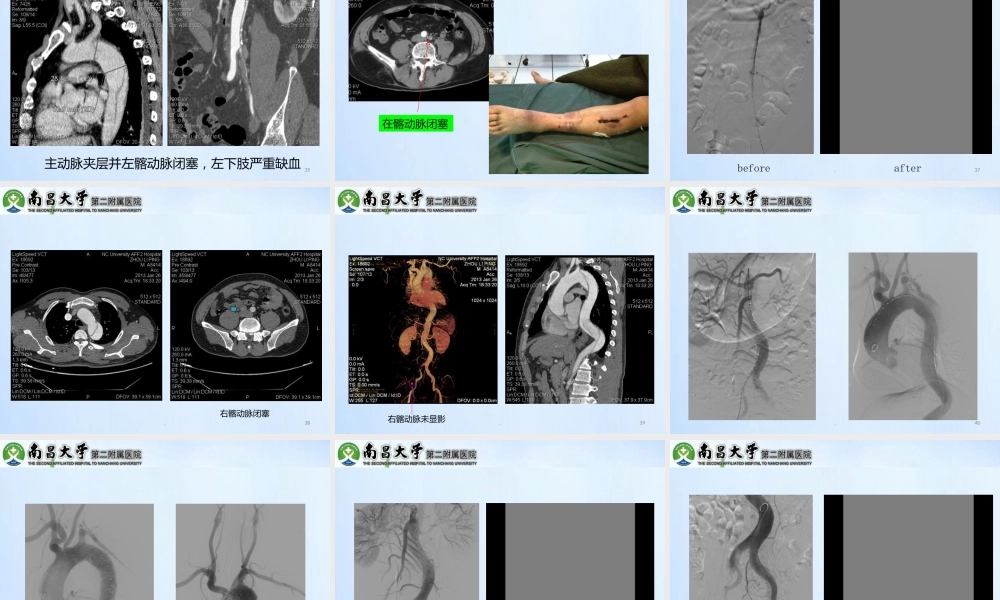

.1概述B型主动脉夹层可侵犯腹腔干动脉(CV)、肠系膜上动脉(SMA)以及肾动脉(RA)等,发生内脏缺血导致肝功能衰竭,缺血性肠炎、肠坏死或急性肾功能不全等Kalko报道B型AD并SMA缺血死亡率高达87%,并RA缺血死亡率50%-70%.2内脏缺血的分型由于主动脉或分支动脉真腔狭窄或塌陷导致内脏动脉缺血由于内膜破裂或断裂引起血肿压迫、内膜卷曲等使得内脏动脉缺血.3内脏动脉(VA)受累分型压,血流部分或不受影响动脉共同供血.4.5VA血供分型真腔供血:VA未破坏或已被压迫,但VA血供仍来源于真腔腔共同供血:VA内膜破裂及少数VA内膜断裂,真假腔均通畅假腔供血:VA内膜断裂,真腔被完全压迫,血液来着假腔血:VA未破坏但是被完全压迫;内膜断裂内膜套叠;VA远端血栓形成等.6.7病理机制起的脏器缺血.8病理机制层并可检测...